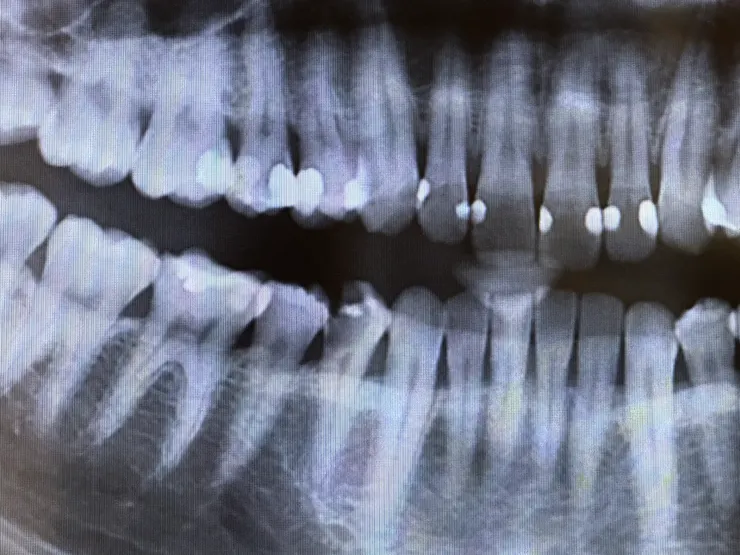

案例二